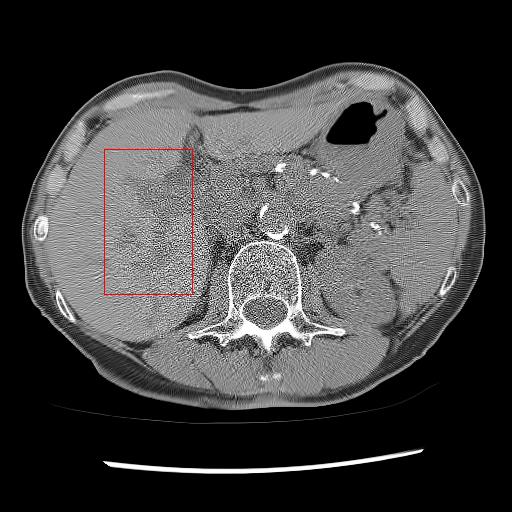

As shown in Table 3, DIP has exhibited the worst performance among all the methods. On the other hand, the ConsensusNet yielded a better FID and TML than BM3D but a lower PSNR and SSIM than other methods. The ConsensusNet divided the original projection data of the low dose CT image into two subgroups and back-projected to create the noisy input signal. Consequently, the noisy input image is much noisier than the original LDCT image. Also, the structural loss occurred during the generation of noisy images, so as a result, the PSNR and SSIM of this method are lower than other methods. Texture matching loss (TML) is used to measure the texture difference between the reconstructed and original images. The lower value of TML indicates that the generated texture is similar to the original. In comparison, FID estimates the distance between the distribution of the generated image and real images. A lower value of FID signifies the generated images are more similar to the original image. The current deep learning era demands a denoised image with a low value of these metrics. These denoised images may be used as input for other image classification tasks or segmentation networks. In this regard, the ConsensusNet is superior to the BM3D because it uses the deep neural network’s expression power. CycleGAN is another powerful unsupervised method for image-to-image translation; it achieved better performance than the other methods. However, CycleGAN has a lot of bottlenecks, e.g., longer training time, computation power, hyper-parameter tuning, etc. All these bottlenecks make CycleGAN ill-suited for practical deployment. Meanwhile, our proposed method has achieved the highest PSNR, SSIM, FID, and VIF among all the other methods. Next, we compare the result of denoising visually in Figure 6. It can be observed that the proposed method performs significantly better than the other unsupervised methods. BM3D output produced a blurry denoised image and contained many splotchy artifacts. The same blurriness can be observed in the output of ConsensusNet, and DIP, although noise suppression is adequate, and splotchy artifact is absent. In the output of CycleGAN, we can observe the presence of residual noise, especially in the high noise regions. Next, we identified one low attenuated lesion in the sample image and marked the lesion with a red colour bounding box. The zoomed view of the region inside the bounding box is given in Figure 7. In our method’s output image, the lesion’s visibility is enhanced significantly than in other methods. Despite being an unsupervised method, the visibility of the lesion is comparable with the original NDCT image. Also, from the zoomed view, we can perceive that our method has suppressed the granular pattern without losing the original image’s texture.

Refer to caption

(a) LDCT

(b) BM3D

(c) DIP

(d) CycleGAN

(e) ConsensusNet

(f) Proposed

(g) NDCT

Figure 7: Comparison of denoising performance of different network. Zoomed view of the region inside the bounding box shown in the images for Figure 6